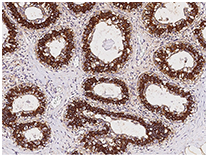

Anti-FASN Ab, Rabbit pAb: (Cat#: 100685-T10)

Immunochemical staining of human FASN in the human breast.

Immunochemical staining of human FASN in the human breast. Image Credit: Sino Biological Inc.

• Applications: IHC-P, ICC/IF